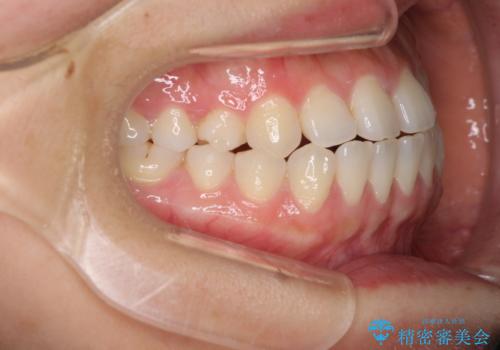

- 上下の前歯の隙間を気にして来院された患者様です。

インビザラインを用い、上下歯列のスペースを閉じていくこととしました。

治療期間中は奥歯がほとんど咬めない状態が続き、食事に大変苦労されました。

最終的には隙間もしっかりと閉じ、奥歯も咬みやすい状態でしあげることができました。